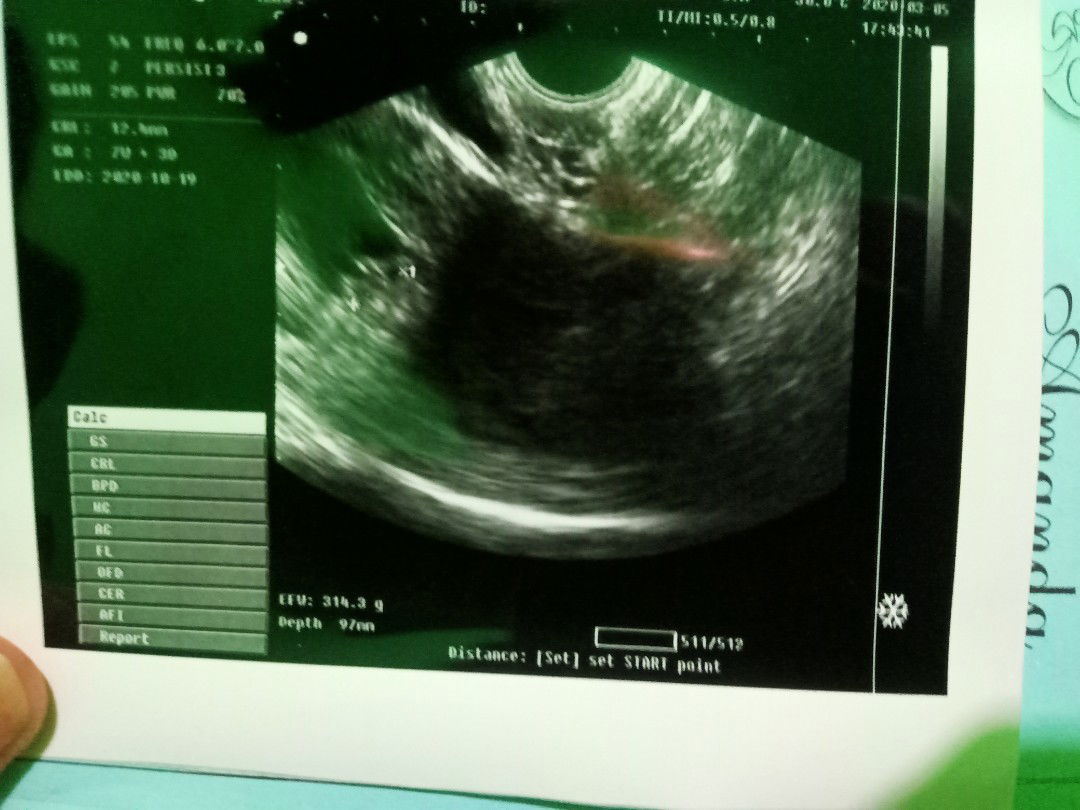

hallo bunda saya lgi hamil 8minggu tp sering ngeflek keluar darah udh coba usg dokte bilang gk keguguran cumn janin nya aja lemah..apa ada bunda2 disini yg ngalamin seperti saya.??